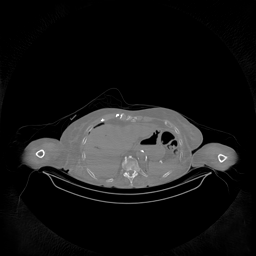

III-D Real Clinical Data Experiment

The experimental results on clinical head data are shown in Fig. 4. The reference images were reconstructed using the fast iterative shrinkage-thresholding algorithm (FISTA) with total variation regularization from non-truncated projection data. In the WCE reconstructions (Fig. 4(b)), severe truncation prevents accurate recovery of anatomical structures outside the FOV. Despite being trained solely on simulated data with a domain gap, all deep learning models can restore a substantial portion of the missing anatomy. Among them, the diffusion-based methods recover soft-tissue boundaries more faithfully than the conventional deep learning approach FBPConvNet, highlighting their stronger image generation capability. However, cDDPM reconstructions exhibit more noticeable noise than those from other methods, consistent with the simulated data results. The patchDiffusion model introduces artifacts within the FOV, likely due to its patch-wise processing strategy. While I2SB shares the same limitations as other diffusion models in perfectly restoring soft-tissue detail, it produces fewer residual noise patterns and fewer artifacts within the FOV boundaries. Overall, Fig. 4 demonstrates the strong efficacy of I2SB in reconstructing real CBCT data.